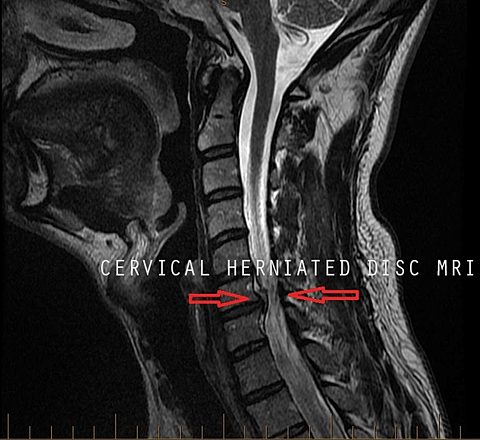

MRI OF THE CERVICAL SPINE WITHOUT CONTRAST

C6-C7: Mild posterior disc bulging with uncovertebral joint spurring and facet hypertrophy resulting in mild bilateral foraminal stenosis. C7-T1: No disc herniation or bulging. ... Retrieve Doc

Measurement Of Cervical Intervertebral Disc Bulge

Measurement of Cervical Intervertebral Disc Bulge +1Amirouche, F; (FSUs) and two C5-C6 FSUs. The IVD were left intact. The specimens were prepared so that a smooth level surface Anterior IVD bulging increased until ... View Document

1 Prevalence Of Annular Tears And disc Herniations On MR ...

3 “All 12 volunteers older than 45 years had at least one bulging disk.” 42 bulging disks were found in 22 volunteers: 33% were at the C5–C6 disk space ... Content Retrieval